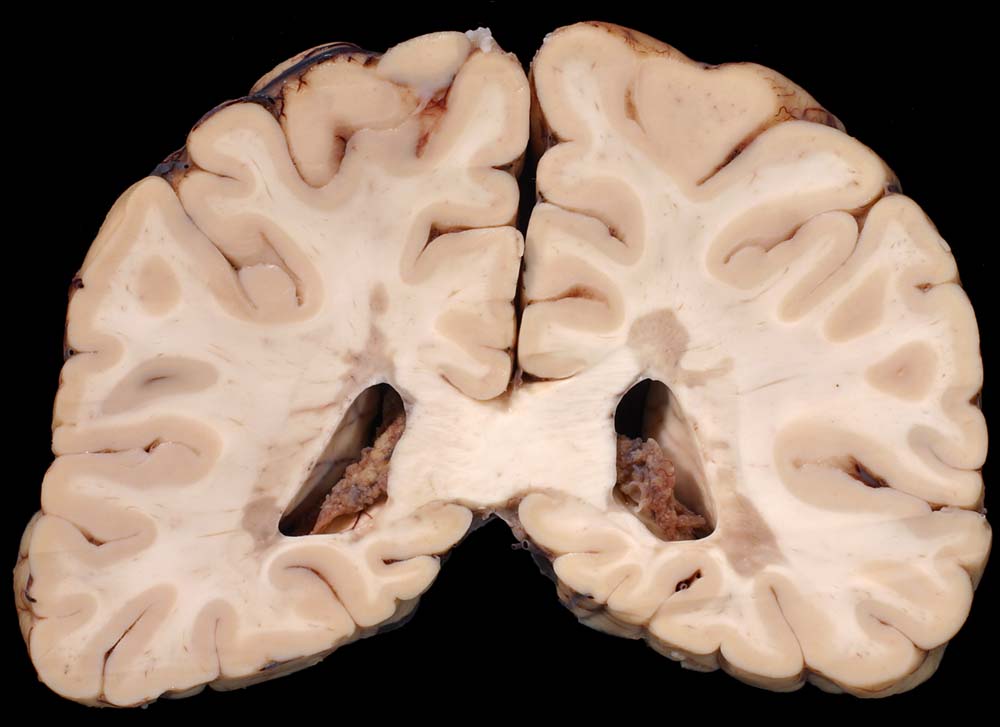

Periventrikuläre irregulär begrenzte Grauverfärbung des Marklagers.

Multiple Sklerose (Erstdiagnose vor 30 Jahren) mit spastischer Paraparese und neurogener Blasenmotorikstörung.